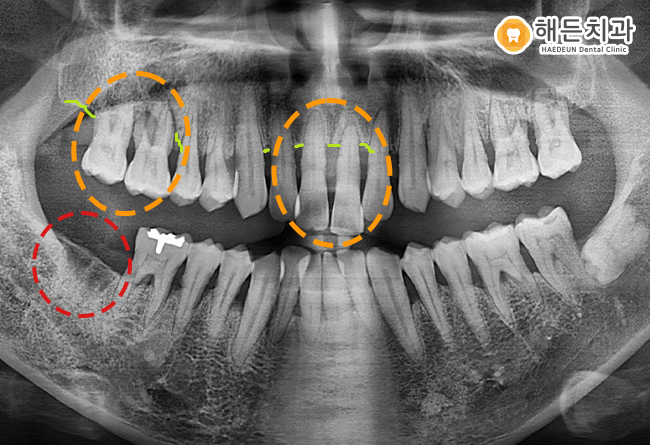

위 사진은 해든치과에 내원하신 조*수 님의 파노라마 사진입니다.

위의 환자분은 치주염이 심한 상태로 본원을 찾아주셨습니다.

파노라마 사진을 촬영해 검진해보니, 전체적으로 치주질환이 진행된 상태였으며

치주염으로 인해 잇몸 뼈 라인이 많이 내려가 있는 상태였으며, 흔들리는 치아도 다수였습니다.

전체적으로 치아 상태가 좋지 않아 치료가 필요한 치아가 많았지만,

우선적으로 상태가 가장 심각하고 환자분께서 불편감을 겪고 계신

오른쪽 위의 어금니2개와 위의 앞니2개를 발치하고 임플란트 식립을 진행하기로 했습니다.

뼈가 녹아 연두색 표시의 잇몸뼈 라인을 보시면, 잇몸라인이 치아 뿌리부분까지 내려앉은 상태로

치아가 거의 대롱대롱 매달려 있는 상황이었습니다.

더불어 기존에 상실되어있던 오른쪽 아래 빨간색 동그라미 표시의 두번째 큰 어금니 자리에도

임플란트 식립을 함께 진행하기로 했습니다.